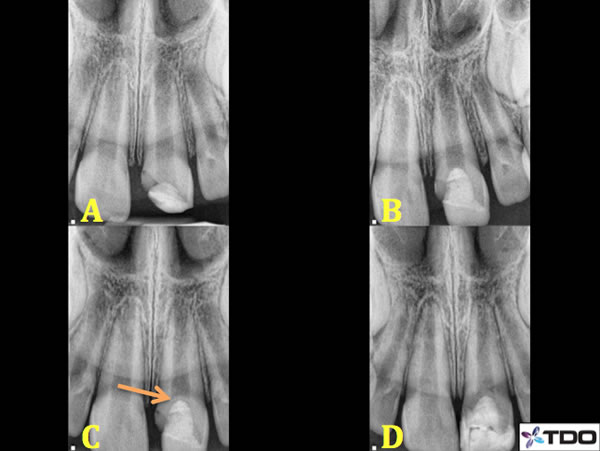

Figure 8. A 7 year old male presented to our office with a complex crown fracture 2 days following a skateboarding accident. His general dentist placed a temporary composite filling over the exposed pulp the day before our consultation although there was no placement of any pulp capping material (A). The roots of 7-10 are immature with open apices. Pulpotomy was performed. I removed the composite filling and 3mm of pulp tissue until reaching healthy pulp. The bleeding was arrested and I placed a layer of MTA, which was allowed to set for a few days prior to covering the material with dual cure composite (B). 4 month recall (C) reveals evidence of a calcific bridge (orange arrow) and continued root formation. Patient remained asymptomatic at the one year recall (D). Further root formation is evident.